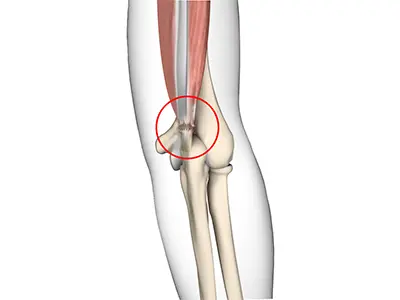

Tennis elbow Surgery

Tennis elbow is a common name for the elbow condition lateral epicondylitis.